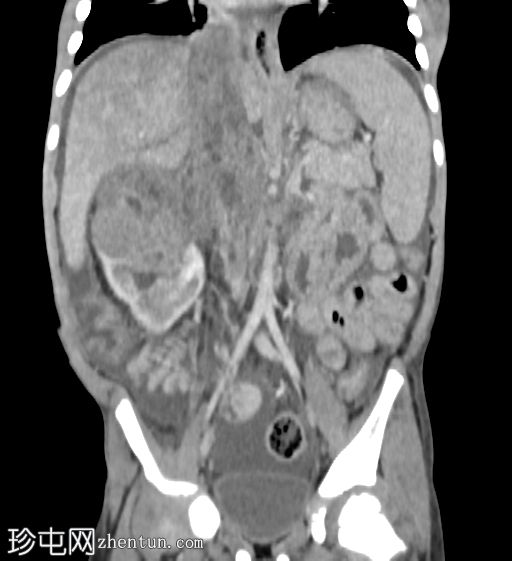

轴位增强扫描(门静脉期)

右肾极间区可见一巨大异质性肿块,伴坏死区域。

病灶延伸至扩张的右肾静脉、右下腔静脉和右心房。

轻至中度腹水。

可见亚厘米级腹主动脉旁淋巴结。

右侧少量胸腔积液,右下叶可见一小块强化胸膜下结节。

影像学特征提示右肾母细胞瘤(Wilms瘤),伴肿瘤血栓形成至下腔静脉和右心房。